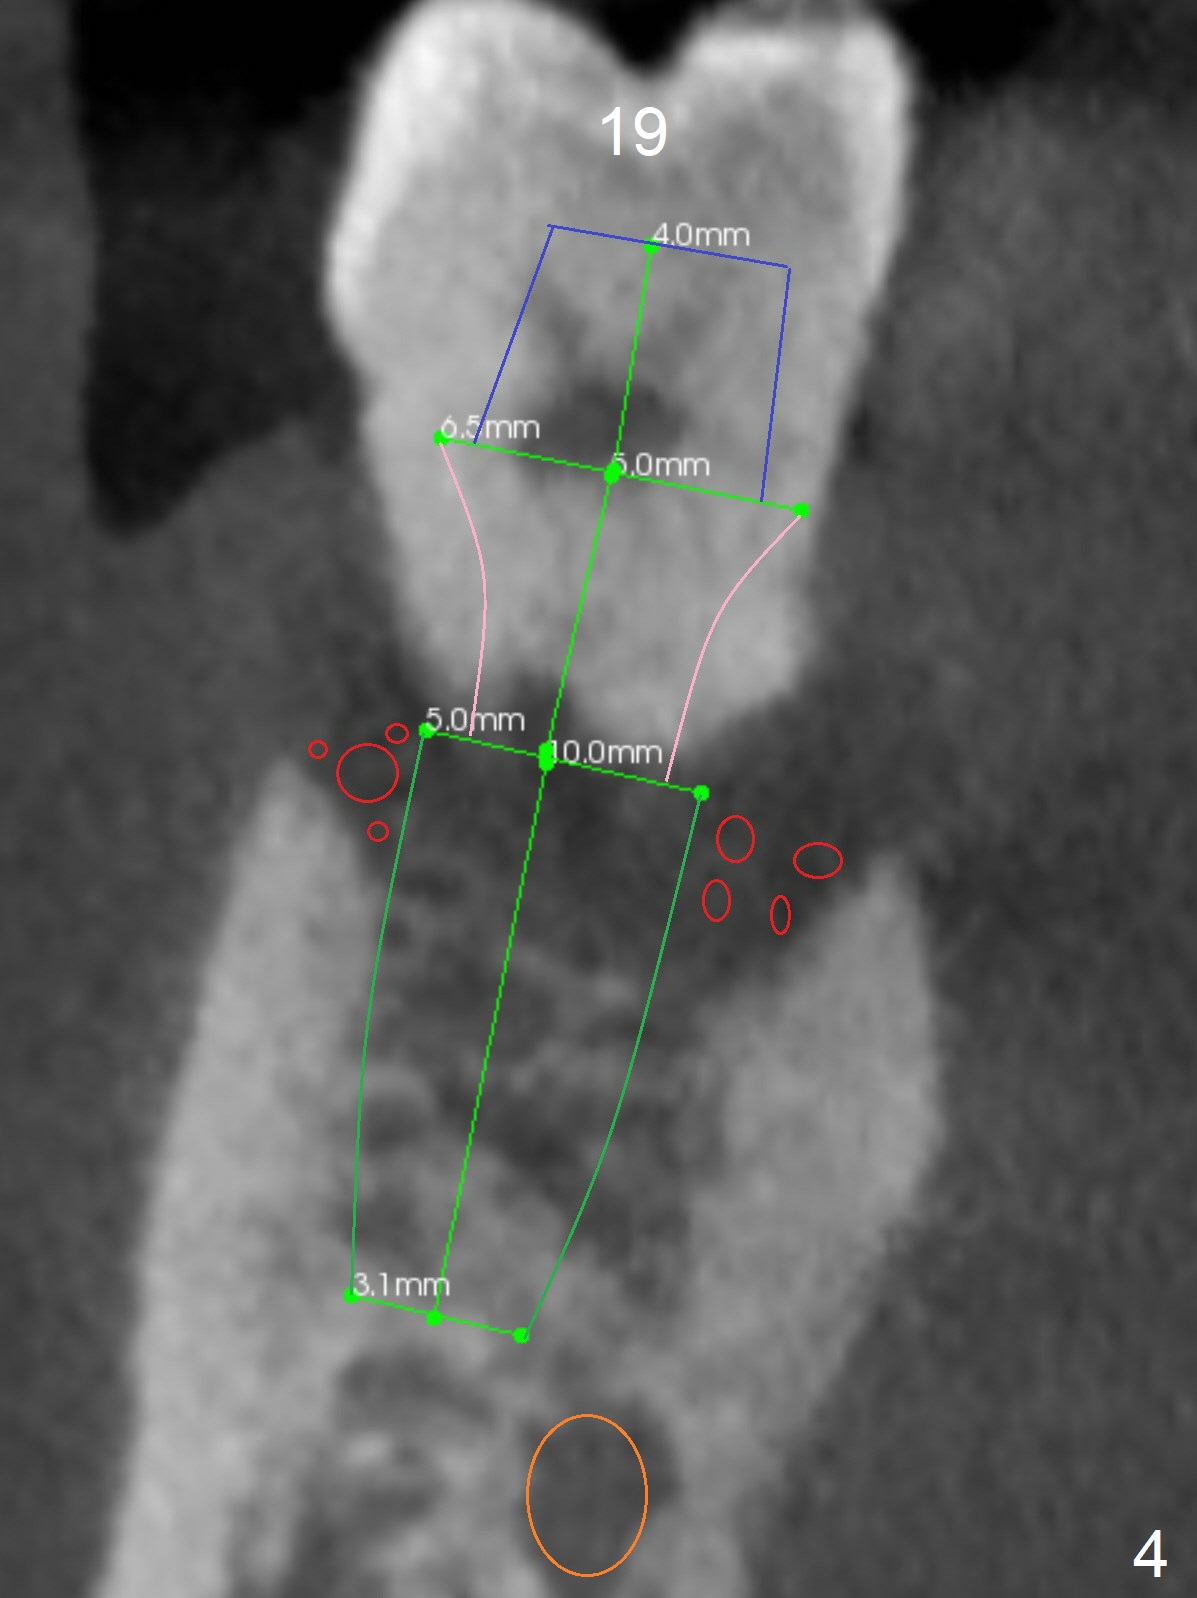

A 36-year-old man develops periodontal abscess at #19 and 20 after scaling & root planing. Since the site of #20 is close to the Mental Nerve, 3.8 mm tap or dummy implant will be used to form osteotomy instead of drills (Fig.1,3). While an implant will be placed in the middle of the socket #20, an implant will be placed as buccal as possible at #19 (Fig.4). If primary stability at #20 is poor, extract the tooth #21 and place a 3.8x10 mm lingually (Fig.2). PRF membrane will be placed prior to bone graft after implant placement (Fig.3 yellow).